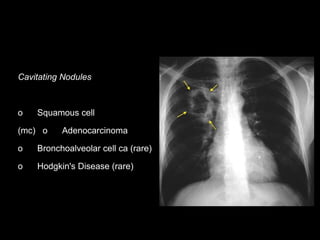

Cavitating Nodules

o Squamous cell

(mc) o Adenocarcinoma

o Bronchoalveolar cell ca (rare)

o Hodgkin's Disease (rare)